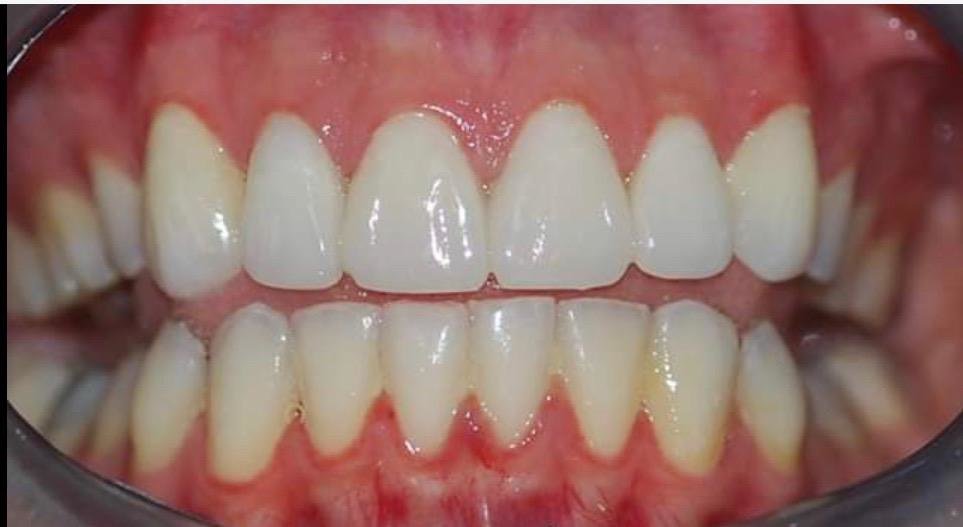

About Live Implants Nicaragua Virgil Mongalo DMD is a dental implant surgeon, past professor of implant surgeries at the University of Miami and the University of Florida has opened a surgical implant center in Managua. This is a state of the art facility consisting of equipped with Ct-scan, 3D Printer, zirconia milling machine, 8 surgical rooms, and USA sterilization controls. His team consists of implant surgeries professor accredited... (Show more)